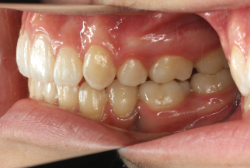

「出っ歯を治したい」という主訴で来院したケースです。診断の結果、「2級1類の上顎前突+軽度叢生」と判明しました。2級というのは、基本的に出っ歯の噛み合わせになっていることを言います。その中でも上の前歯が著しく外に反っているケースを、「1類」といいます。初診時の横向きの写真を見ると、それがはっきり分かります。上の前歯に押されて唇も膨らんで、審美線をかなりオーバーしています(審美線とは、鼻の先端と顎の先端を結ぶ線のことで、この線よりも唇は内側にある方が良いとされています)。

このような症状の場合は、前歯を内側に入れるためにかなり大量の隙間を必要とします。通常は上下左右の小臼歯を抜歯させていただくのが正解です。治療後は歯の角度が正しくなっただけでなく、唇の審美性が大幅に改善しました。もちろん噛み合わせ的にも正しい状態が確立しています。